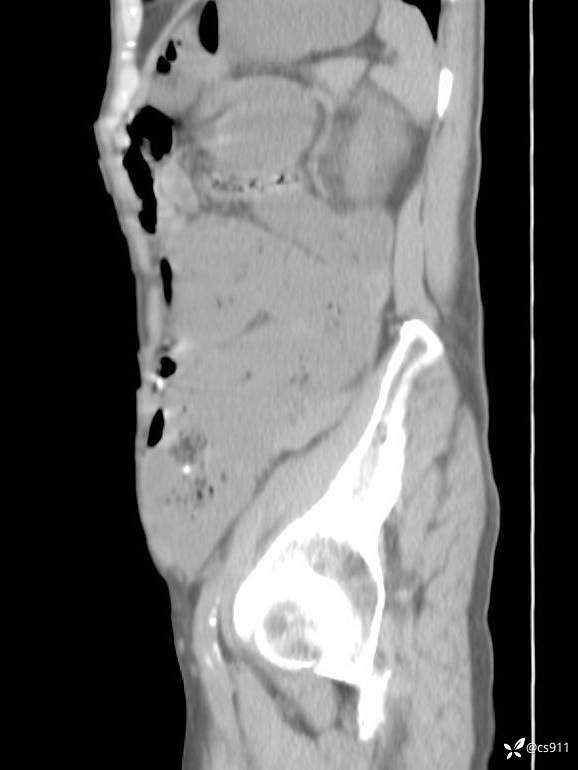

急腹症之急诊CT,原因?答案公布

男,77岁,腹痛、腹胀伴恶心呕吐1天。呕吐胃内容物,非喷射性呕吐,有咖啡色样胃内容物,诉有胃穿孔病史。查体:全腹平,下腹部压痛,全腹无反跳痛,叩诊呈浊音,移动性浊音阴性,肠鸣音减弱,1-2次/分。肛检:直肠未扪及明显肿物,可触及大量粪块。

T 36.6℃ P 80次/分 R 26次/分 BP 100/60mmHg

白细胞(WBC) H 14.55 10e9/L 4-10

红细胞(RBC) 4.58 10e12/L 4.3-5.8

中性粒细胞百分率(NEUT%) H 85.7 % 40-75

血淀粉酶(AMY) HH 1859 U/L 35-135

癌胚抗原(CEA) H 27.44 ng/ml 0-5

呕吐物 潜血试验 * 阳性 阴性

患者轮椅入室检查神志清楚, 能配合摆位和呼吸